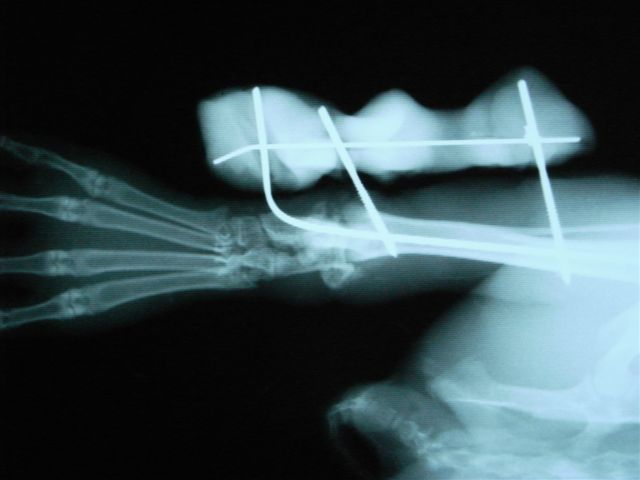

うさぎ、踵の骨折、骨髄内にピンをいれて固定。

関節に近い骨折だと固定が関節ごと固定するので稼動域が狭くなりやすい。

エポキシパテと髄内ピンで整復して固定